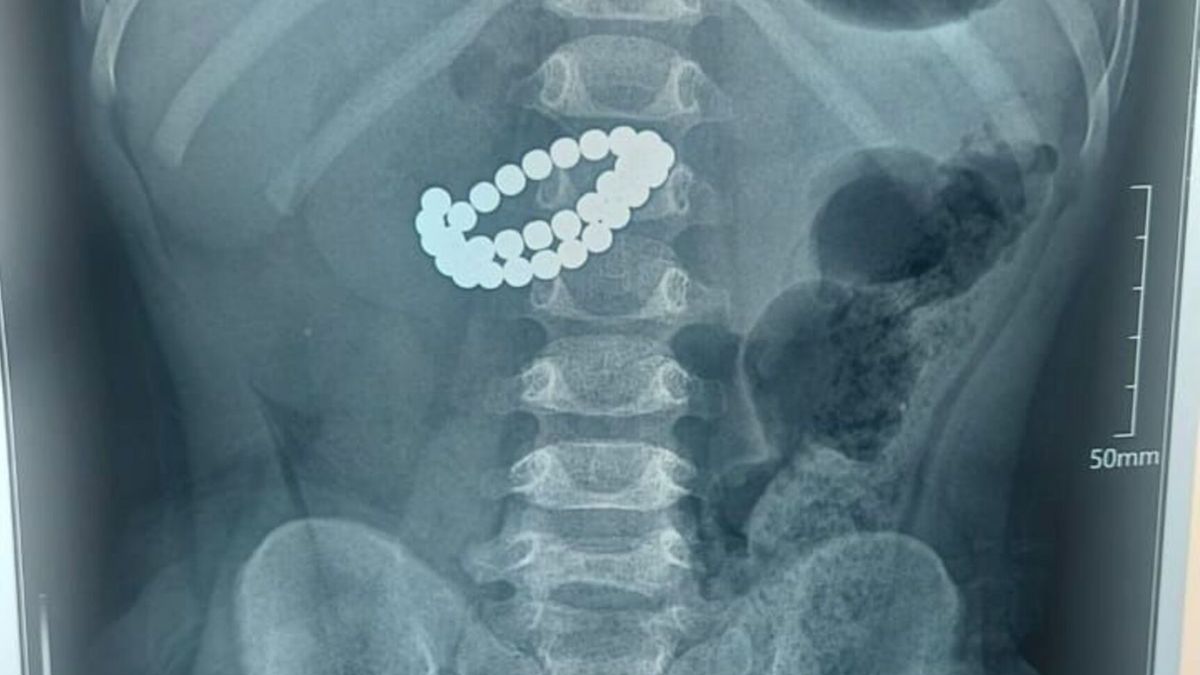

Алматыда бір жасар бала 31 магнит жұтып қойған

Фото: Алматы қаласы әкімдігінің баспасөз қызметі

Алматыда хирургтер 31 магнит жұтып қойған баланың өмірін сақтап қалды, деп хабарлайды KAZ.NUR.KZ қала әкімдігінің баспасөз қызметіне сілтеме жасап.

Қоғамдық денсаулық сақтау басқармасының өкілдерінің хабарлауынша, Алматының Балаларға шұғыл медициналық көмек көрсету орталығында 31 магнит жұтып қойған сәбиге шұғыл ота жасалды.

Қабылдау бөліміне 1 жас 9 айлық бала өте ауыр жағдайда жеткізілген. Тексеру нәтижесінде дәрігерлер "ішектегі бөгде заттар – 31 магнит, жіңішке ішектің көп жерден тесілуі, перитонит" диагнозын қойды.

Баланың өмірін сақтап қалудың жалғыз жолы – шұғыл хирургиялық ота жасау еді. Дәрігерлер ортаңғы лапаротомия жасап, құрсақ қуысы ағзаларына толық тексеру жүргізді. Ота барысында магниттер ішектен алынып, жіңішке ішектегі көптеген тесік тігілді, құрсақ қуысы тазартылып, дренаж орнатылды. Сонымен қатар ішекке трансаналдық интубация жасалды.

Орталық хирургі Асқар Ризвановтың айтуынша, магниттердің басты қаупі – олардың ағзаға бөлек-бөлек түскенімен, ішекте бір-біріне тартылып, ішек қабырғасын қысып қалуында.

"Магниттердің арасында ішек қабырғасы қысылады, қан айналымы бұзылады, тіндер жансызданады, тесік пайда болады. Соның салдарынан санаулы сағаттардың ішінде перитонит дамуы мүмкін. Ата-аналар көбіне баланың жағдайы қаншалықты жылдам нашарлайтынын аңғармай қалады", - дейді хирург.